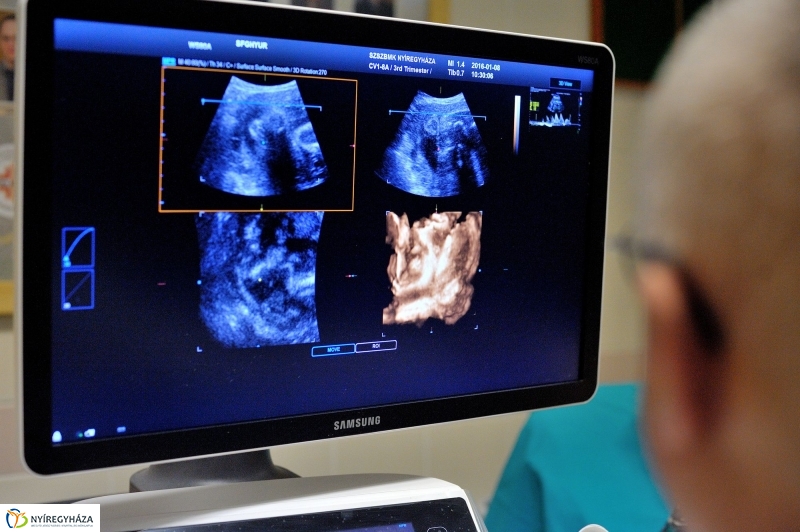

A korszerű ultrahang segíti az orvosok munkáját a terhesgondozás egész ideje alatt, az ezekhez kapcsolódó valamennyi szűrővizsgálat során, és a nőgyógyászati beavatkozások előtt is. A pontos képalkotás elengedhetetlen a precíz diagnózishoz.

Dr. Angyal Géza főorvos, az ultrahanglabor vezetője szerint sokkal és mindenben többet tud ez a berendezés, mint az eddig használt készülékek. A szakember hozzátette, olyan lehetőségeket nyit meg számukra, amelyet egy ennél kisebb tudású géppel lehetetlen elérni, lehetetlen reprodukálni. Olyan képalkotásra képes a gép, ami Nyíregyházán korábban még nem volt.

A Jósa András Oktatókórház Szülészet-nőgyógyászati Osztályán az elmúlt évben több mint 15 ezer 500 ultrahangvizsgálatot végeztek a szakemberek, akik rendszeresen részt vesznek szakmai továbbképzéseken és világkongresszusokon is. A Nyíregyházára került új eszköz a képeket képes digitálisan tárolni, ami a betegellátás színvonalának javulása mellett lehetővé teszi az adatok tudományos feldolgozását, illetve azt, hogy szükség esetén az itteni orvosok a világ bármely részén rendelő kollégájukkal konzultálni tudjanak.